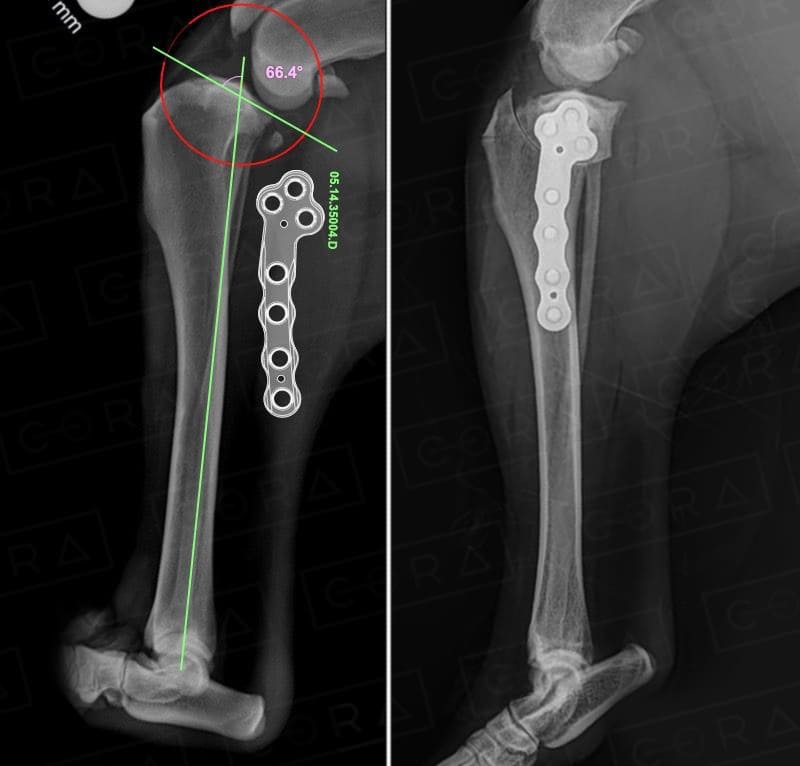

TPLO (Tibial Plato Leveling Osteotomy) Osteotomia de Nivelamento do Platô Tibial

A TPLO é uma técnica cirúrgica bastante utilizada para tratar a ruptura do ligamento cruzado cranial em cães, uma das lesões ortopédicas mais comuns, que afeta cães de todas as raças e tamanhos. (RLCCR). O ligamento cruzado cranial, localizado no joelho, tem a função de estabilizar a articulação femorotibial, evitando o deslizamento do fêmur sobre a tíbia. Quando ocorre a ruptura desse ligamento, o joelho torna-se instável, causando dor e claudicação (mancar).

Ao mudar o ângulo da tíbia, a TPLO modifica a biomecânica do joelho e elimina a necessidade do ligamento cruzado cranial para estabilizar a articulação. Isso impede que a tíbia deslize cranialmente em relação ao fêmur quando o cão coloca peso na perna.

1. Corte da Tíbia: A cirurgiã realiza um corte curvo na tíbia e, em seguida, faz uma rotação no segmento cortado para mudar o ângulo do platô tibial, que é a parte superior da tíbia onde o fêmur se articula.

2. Fixação: Após a rotação, o osso é fixado com uma placa e parafusos, promovendo a estabilização da articulação.

Em platôs extremamente altos (maiores de 40 graus), a TPLO deve ser associada a outra técnica ou a um duplo corte, para evitar uma rotação excessiva do platô tibial.